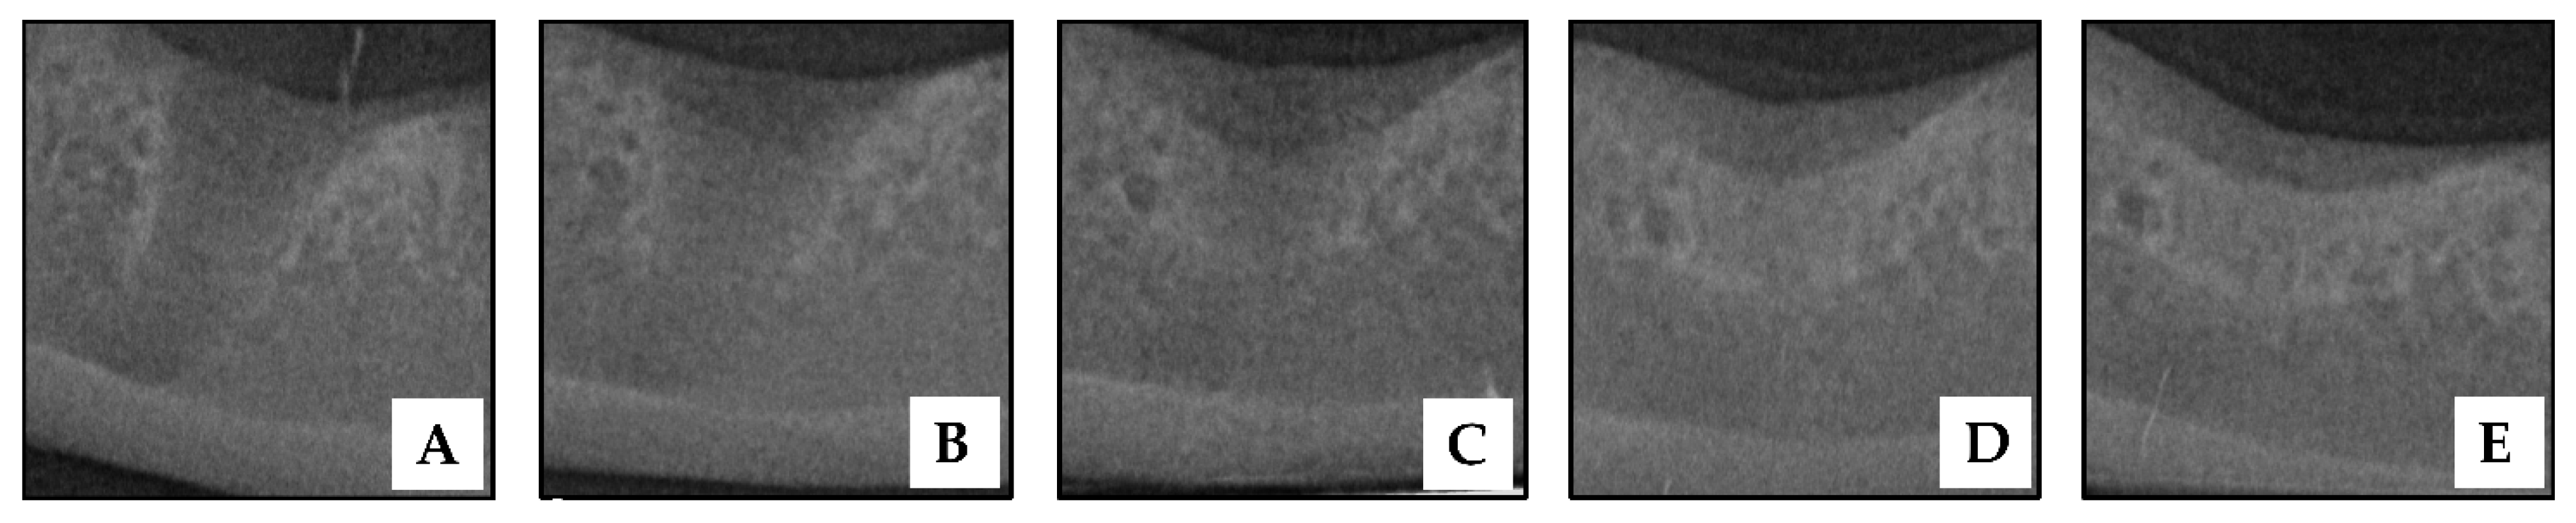

3.3. Radiographic Findings and Grading of Post-Extraction Socket Preservation with HAP Hydrogel

3.4. Bone Height Analysis of Post Extraction Socket Preservation with HAP Hydrogel